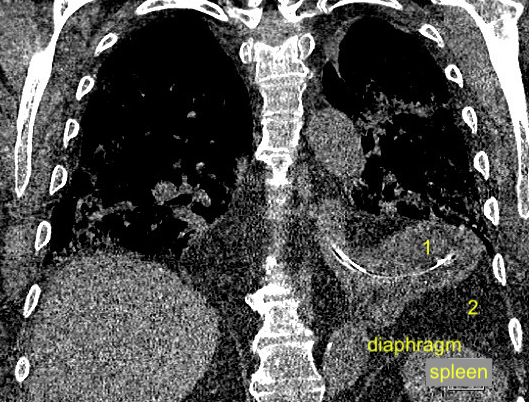

What are structures labeled 1 and 2 (same structures in both images)?

Spleen and diaphragm are difficult to see in this still image, so those are labeled

What are structures labeled 1 and 2?

With CT scan, we see that

-structure #1 is the stomach (with NG tube)

-structure #2 is soft tissue

Answers to above questions - CXR and POCUS labeled here

This is due to a hiatal hernia, with upper portion of the stomach passing above the diaphragm and into the thorax.